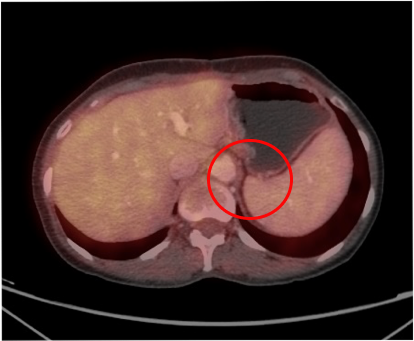

Эпителиальная мезотелиома брюшины, ТxN0M0. Циторедуктивная операция (оментэктомия, париетальная перитонеумэктомия тотальная, экстирпация матки) + HIPEC (цисплатин + доксорубицин) от 08.08.2023. Химиотерапией HIPEC называют новаторскую разновидность лечения злокачественных новообразований. Эта процедура подразумевает прямое воздействие на опухолевые клетки разогретыми химиопрепаратами. Прогрессирование (ПЭТ/КТ от 21.09.2023; до операции ПЭТ/КТ не выполняли): инфильтративное образование с повышенной метаболической активностью РФП по брюшине слева на уровне ножки диафрагмы/ дна желудка (SUVmax — 5,34), SUVmax (Maximum Standardized Uptake Value) — максимальный показатель степени накопления радиофармпрепарата (РФП) в выделенной зоне интереса; метастазы во множественных внутригрудных лимфатических узлах (бронхо-пульмональные слева и справа, парастернальный слева с SUVmax 3,47 — 4,6). Таргетная терапия Регорафенибом (Стиварга) с 23.09.2023 г. по н.вр. (со снижением дозы до 120 мг/сут. с учетом нежелательных явлений — ладонно-подошвенный синдром легкой степени). Частичный регресс (ПЭТ/КТ от 20.12.2023): нивелирование инфильтративного образования с повышенной метаболической активностью РФП по брюшине слева (ранее на уровне ножки диафрагмы дна желудка определялось образование 11х8 мм с SUVmaх — 5,34), снижение в динамике метаболической активности РФП во множественных внутригрудных лимфатических узлах (бронхопульнональный слева с SUVmaх — 3,6, размерами до 8х6 мм, ранее SUVmaх — 4,6; бронхо-пульмональный справа с SUVmaх — 3,56 размерами до 9х7 мм, ранее SUVmaх — 4,3; парастернальный слева с SUVmaх — 1,6 размерами до 5 мм, ранее SUVmaх — 3,47). Полный регресс (ПЭТ/КТ 19.03.2024; 24.03.2025).